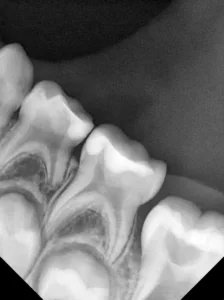

Bei routinemäßigen Röntgenkontrollen ergeben sich manchmal Zufallsbefunde unklarer Genese. So stellt sich beispielsweise bei der Betrachtung der Abbildung 1 die Frage, wie sich ein Zahnhartsubstanzdefekt so schnell entwickeln konnte. Ein weiteres Röntgenbild (Abb. 2), das vor dem Zahndurchbruch aufgenommen wurde, zeigt jedoch, dass es sich in diesem Fall nicht um Karies, sondern um die sogenannte präeruptive intrakoronale Resorption (PEIR) handelt. Für diesen Befund finden sich in der Fachliteratur auch noch andere Bezeichnungen wie „idiopathic external resorption of unerupted permanent teeth“ [1], „intra-follicular caries“ [2], „radiolucent lesions resembling caries“ [3], „occult caries“ [ 4] oder „pre-eruptive caries“ [5].

Jahr vor dem Durchbruch des Zahnes 36.

Das fünfjährige Mädchen stellte sich 2017 zur jährlichen Routinekontrolle vor. Im Rahmen der Untersuchung wurden Röntgenaufnahmen der Milchmolaren gemacht (Abb. 2). Der klinische und radiologische Befund der vor uns früher gelegten Kompositfüllungen war gut, es wurde allerdings eine PEIR an den noch nicht durchgebrochenen ersten bleibenden Molaren festgestellt (Abb. 2). Den Eltern wurde empfohlen, sich unverzüglich bei Beginn des Durchbruchs der ersten Molaren erneut zur Behandlung vorzustellen. Ein Jahr später erschien die junge Patientin schmerzfrei zur Kontrolle. Der Zahn 36 war noch teilweise mit Gingiva bedeckt. Auf einer neuen Röntgenaufnahme (Abb. 1) wurde die PEIR-Läsion mit unveränderter Größe in pulpanahen Bereichen bestätigt (Grad 3 der Läsion nach Seow). Der Zahnschmelz sah intakt aus, es konnte kein pathologischer periapikaler Befund bei den noch nicht ausgewachsenen Zahnwurzeln festgestellt werden. Daraufhin wurden die verschiedenen Behandlungsmöglichkeiten von Fissurenversiegelung bis Vitalerhaltung der Zahnpulpa mit den Eltern des Kindes besprochen.